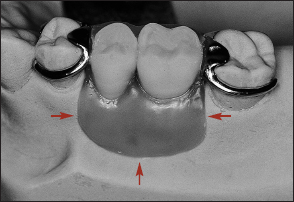

Another method for categorizing removable partial dentures relates to the manner of their support. A partial denture that receives support from natural teeth at each end of the edentulous space or spaces is a tooth-supported removable partial denture (Fig 1-6). Although the denture base contacts the adjacent soft tissues, the prosthesis does not receive significant vertical support from the residual ridge.

Fig 1-6 A tooth-supported removable partial denture.